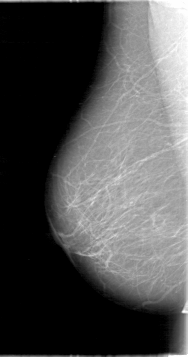

D_4091_1.LEFT_MLO

LEFT_MLO LINES 5386 PIXELS_PER_LINE 3106 BITS_PER_PIXEL 12 RESOLUTION 43.5 OVERLAY